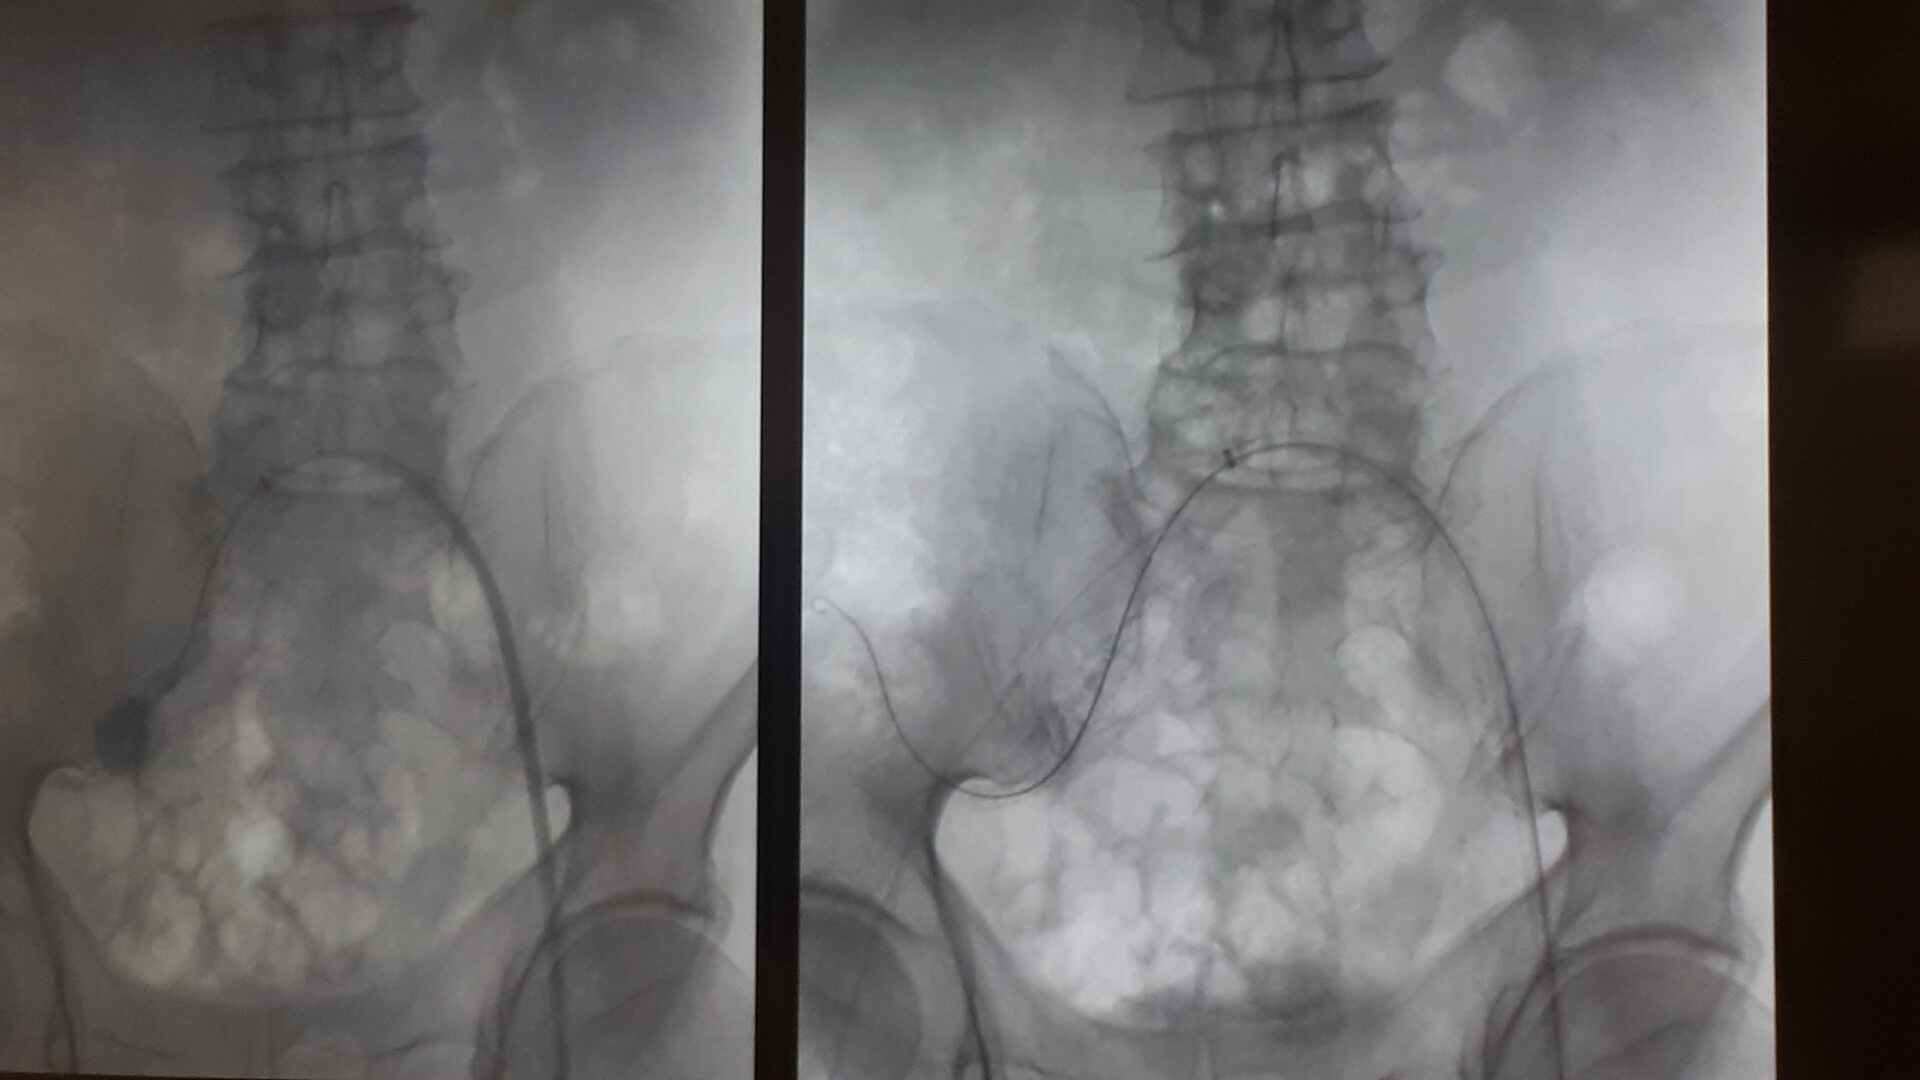

Pierwszą w Polsce operację wszczepienia nowego rodzaju stentgraftu, czyli specjalnej protezy do zabezpieczania tętniaków aorty, przeprowadzili lekarze z Uniwersyteckiego Szpitala Klinicznego w Białymstoku.

Chodziło o tętniaka tętnicy biodrowej u 64-letniego pacjenta. Operację przeprowadzono w minioną środę (10.04) w Klinice Chirurgii Naczyń i Transplantacji USK. Pacjent czuje się dobrze i niedługo wychodzi ze szpitala.

Rozwiązaniem okazał się nowy rodzaj stentgraftu, czyli specjalnej protezy wszczepianej do tętnic. "Jest to stentgraft, który jest jednocześnie i miękki, i na tyle sztywny, że się do tego celu dobrze nadawał" – powiedział. Zwrócił przy tym uwagę, że stosowane już standardowo stentgrafty są albo sztywne, albo elastyczne i do zabezpieczenia tętniaka w takim miejscu się nie nadawały.

Do tego od wewnątrz stentgraft jest pokryty heparyną, co ma zapewnić jego długotrwałą drożność i zapobieganie zakrzepicy. - Zakładamy, że stentgraft posłuży pacjentowi również na długie lata – dodał kierownik Kliniki Chirurgii Naczyń i Transplantacji USK w Białymstoku. Przyznał, że takie umiejscowienie tętniaka jest rzadkie, w statystykach białostockiej kliniki trafia się 2-3 razy do roku. Zoperowany z użyciem nowego rodzaju stentgraftu pacjent czekał na to dwa miesiące. Sama proteza kosztuje ok. 9-10 tys. zł. Stosowane dotąd inne ich rodzaje są średnio dwa razy tańsze.